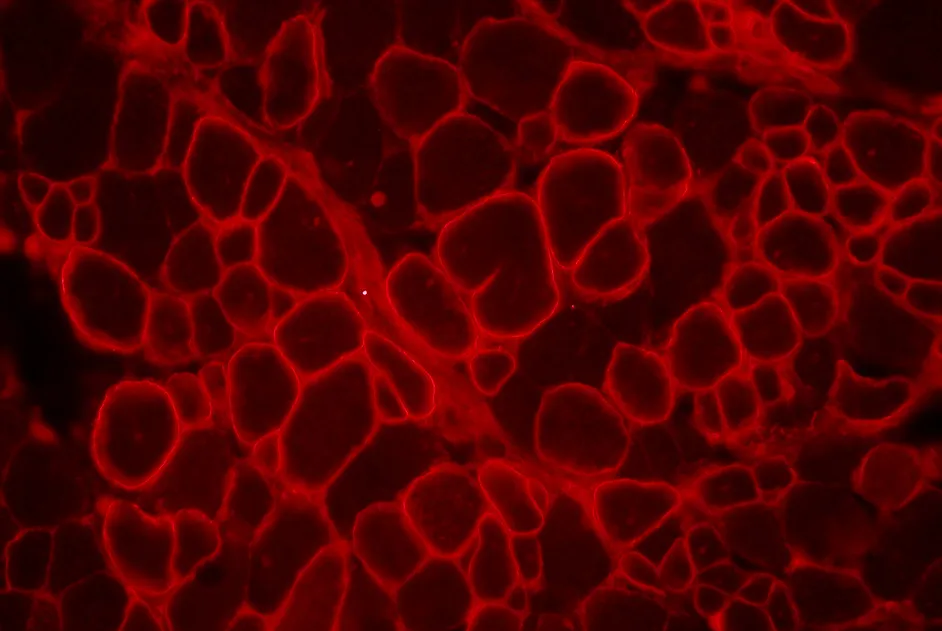

Granulomatose septique chronique : autorisation pour l’essai de thérapie génique de Généthon

Généthon obtient le feu vert de l’agence britannique du médicament (MHRA) pour le démarrage d’un nouvel essai clinique pour un déficit immunitaire héréditaire.